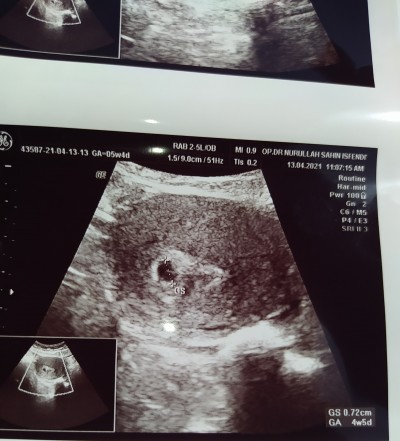

Kese içindeki beyazlık nedir doktorum bilgi vermedi bekliyecegiz dedi bilgisi olanlar yardımcı olabilir mi lutfen burda 4+5 günlük gebeyim ultrason ölçümüne göre

Gebelik haftası 6+2